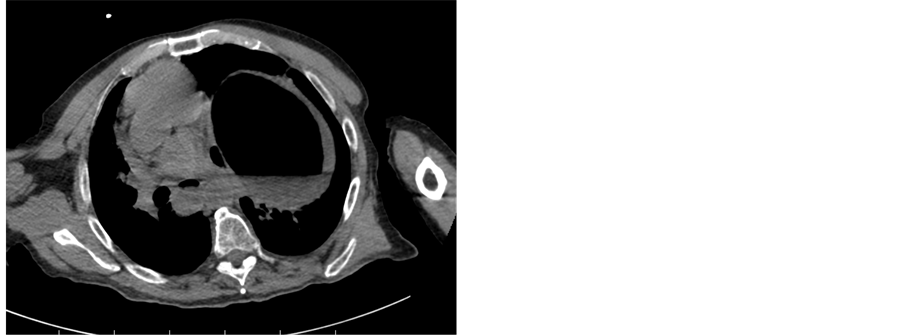

Axial pictures confirmed an enormous colonic distension due to a SV extending from the pelvis up to the thorax nearly at the level of the tracheal bifurcation (Figure 3).

Figure 3. Upper CT scan showing the sigmoid colon reaching the level of tracheal bifurcation and mediastinum moved to the right.